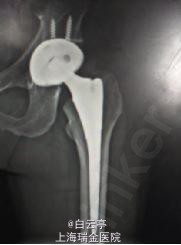

诊断: 左侧髋关节脱位 治疗:左侧髋关节闭合复位术。常规麻醉,将左髋关节外旋,牵拉后内旋,复位后透视下见关节已复位。复位后予以人字形石膏固定1周。

随访:脱位后1月,患者正常生活恢复。 讨论:髋关节脱位是THA术后常见的并发症,主流切口中以后外侧切口发生率较高,直外侧切口较低。术中应尽可能解除假体与人体组织、骨骼的触碰,并做好软组织的平衡。